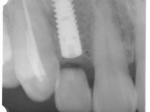

前歯即時埋入症例

術前術前主訴-前歯が腫れて痛い。治療法のうち、ブリッジとインプラントを説明して隣の前歯を削らないですむことからインプラントを選択された。 術前レントゲン術前レントゲン術前レントゲン 抜歯抜歯抜歯を行う。折れていた位置がかなり深い位置であるのがわかる。 歯根も抜歯歯根も抜歯

歯根も抜歯歯根も抜歯歯根も抜歯 抜歯した穴をよく掃除抜歯した穴をよく掃除抜歯した穴をよく掃除(掻爬)後すぐにインプラントを埋入 埋入直後のレントゲン埋入直後のレントゲン埋入直後のレントゲン。上部に見えるのは抜いた歯を利用して両どなりの歯に接着して一時的に使えるようにした。 二次オペ時二次オペ時